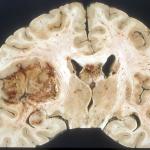

Glioblastoma multiforme (GBM), one of the most dreaded and deadly forms of brain cancer, has been on my mind recently because one of my dog-park friends was recently diagnosed with it.

glioblastoma multiforme